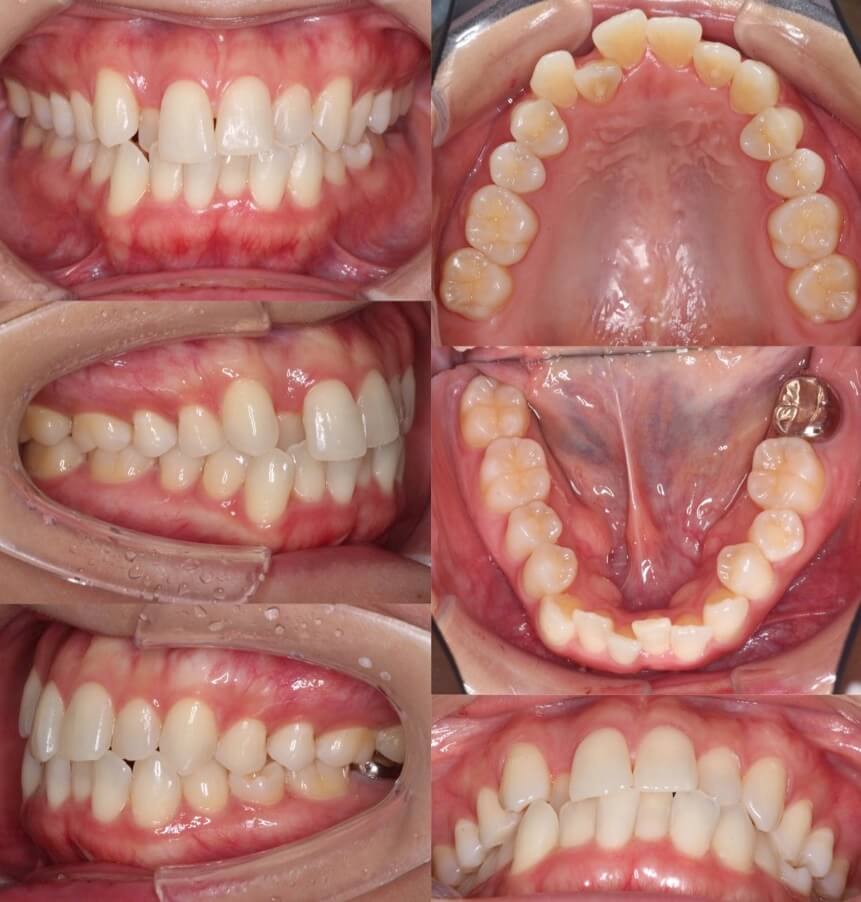

53歳女性・マウスピース型矯正装置

上顎歯列の後方移動を行う際、ふつうは親知らずの抜歯が必要になります。ですが、ミドルエイジの矯正治療では、できるだけ歯数を減らさないように計画を立てます。本治療では、歯科矯正用アンカースクリューを併用することで、達成いたしました。

<症例概要>

主訴:前のねじれと突出

年齢・性別:53歳女性

住まい:千葉県八千代市

症状:下顎後退・上下顎前歯唇側傾斜・叢生・左上7番欠損

治療方針:上顎歯列遠心移動

治療装置:マウスピース型矯正装置(アライナー装置)

固定装置:歯科矯正用アンカースクリュー・II級ゴム

治療期間:1年5か月

アライナー枚数:43+23(7日交換)

リテーナー:上下フィックスタイプ+クリアタイプ

治療費用:990,000(税込)

代表的副作用:痛み・治療後の後戻り・歯根吸収・歯髄壊死・歯肉退縮

▶︎その他の副作用

【治療シミュレーション】

II級ゴムとアンカースクリューからの顎内ゴムで上顎歯列を後方移動させています。